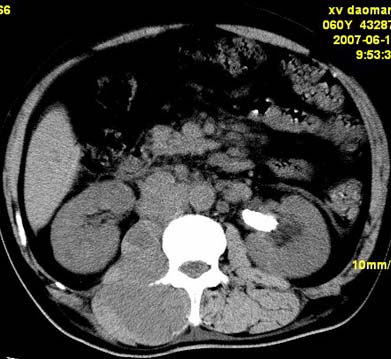

以下是引用还珠格格在2007-6-26 15:05:00的发言:[br]右侧腰大肌、同侧竖脊肌明显肿胀,呈不均匀密度减低影,右肾受压右上前移,脂肪间隙部分消失,另左侧肾盂内可见高密度影,是结石还是造影剂? 不知道病人用造影剂没有?考虑 右侧腰大肌及右侧竖脊肌寒性脓肿形成。[br][br][本贴已被 还珠格格 于 2007-6-26 15:21:35 修改过]

以下是引用小初学者在2007-6-26 15:42:00的发言:[br]1\\右侧腰大肌、同侧竖脊肌脓肿[br]2\\左侧肾盂结石

以下是引用刘明在2007-6-26 16:00:00的发言:[br][br]右侧竖直肌及腰大肌肿胀,脂肪间隙难辨,腹膜后血管旁见多个肿大淋巴结影,椎体附件右侧有压迫吸收、未见硬化迹象,考虑椎旁冷脓肿可能[br]左侧肾盂内可见高密度影,周围有毛刺,本图象是平扫,不是增强,应该是结石[br]

以下是引用hhcckk在2007-6-27 9:41:00的发言:[br]肾周筋膜增厚,胰腺影肥大,楼主是考我们了,我考虑是胰腺炎引起的腰部感染,形成的蓝棕色斑,也称gray-turner征,另外腹膜后怎么这么多的淋巴结,转移也要考虑[br]结核三个月没有骨破坏?寒性脓肿累及到竖脊肌的少见,所以我考虑结核的可能性不太大[br]左肾内高密度影,密度不太均匀,左肾有积水的表现,考虑是结石[br]期待楼主老师的结果